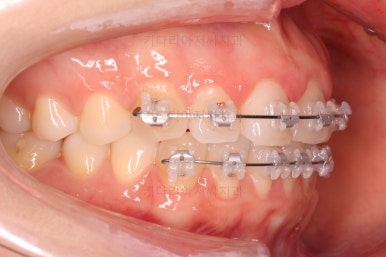

벌써 치료 종료시의 모습입니다.

치료는 총 5개월이 걸렸네요.

일반적으로 부분교정은 6개월 전후로 치료기간이 걸리긴 하고 이번 환자분의 경우는 삐뚤어진 정도가 심한 편이 아니라서 짧게 걸린 편이었어요.

치료결과는 매우 만족하셨습니다.

삐뚤었던, V자로 꺾여있던 나비앞니치아가 가지런해졌어요.

양치질도 훨씬 편해져서 장기적으로 구강건강에도 도웅미 되실 거에요.

다시 틀어지지 말라고 앞니 안쪽에 유지장치를 부착해 주고 마무리를 했습니다.